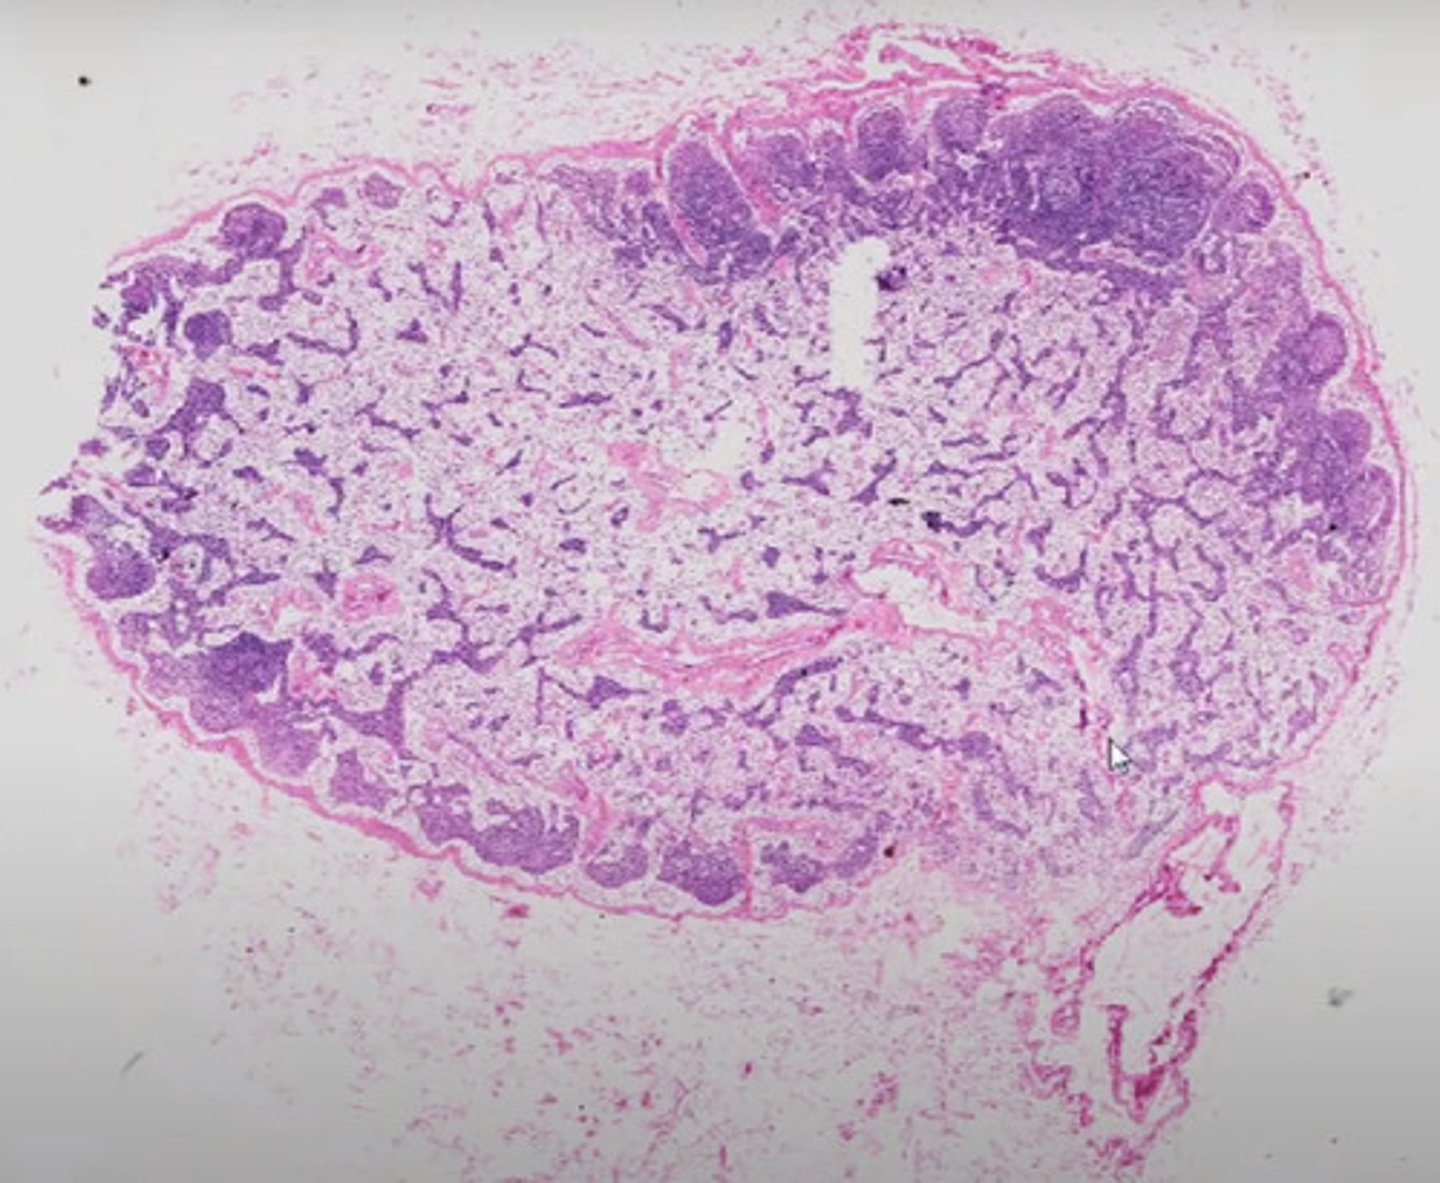

Węzeł chłonny (H+E)

Śledziona (H+E)

Migdałek podniebienny (H+E)